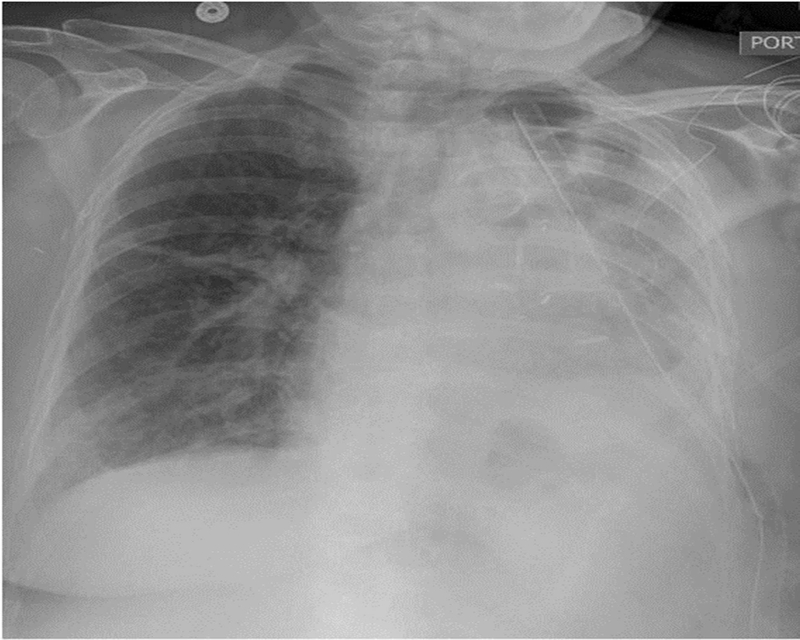

Trong bệnh cảnh chấn thương ngực kín, phổi khá dễ bị đụng dập. Người bệnh có ngay các biểu hiện đau ngực, thở nhanh, khó thở, thiếu oxy, nhịp tim tăng nhanh, suy giảm hô hấp cấp. Nếu cho bệnh nhân truyền dịch thì phù phổi, tràn dịch màng phổi trở nên nặng hơn.

Chẩn đoán đụng dập phổi nhờ X-quang ngực, chụp cắt lớp tùy theo từng tình trạng của người bệnh.